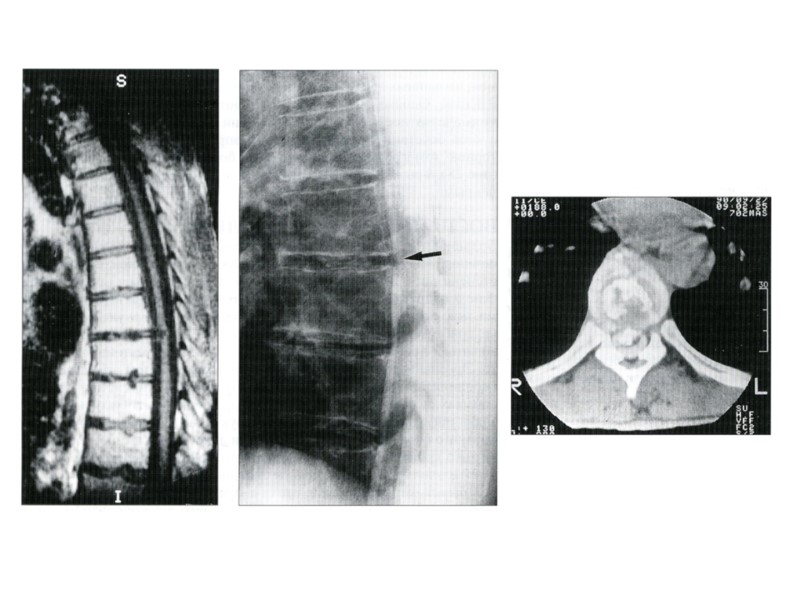

ИЗМЕНЕНИЯ НАДКОСТНИЦЫ Рентгенограмма голени Линейный периостит

Рентгенограмма бедра Слоистый периостит

Рентгенограмма бедра Бахромчатый периостит

Рентгенограмма бедра Кружевной периостит

Рентгенограмма голени Игольчатый периостит

Рентгенограмма бедра Периостальные наслоения в виде так называемого козырька